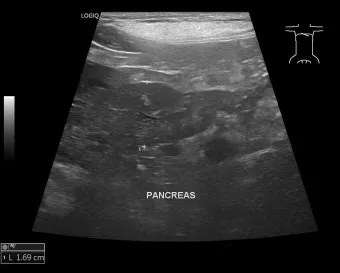

감염성 복막염은 주로 다른 장기의 염증이 확산되면서 발생해요. 예를 들어, 심한 췌장염이나 담낭염이 주변 복막으로 번지는 경우죠. 이런 경우엔 원발 질환 치료와 함께 복막염 관리를 동시에 해야 해서 치료가 더 복잡해집니다.